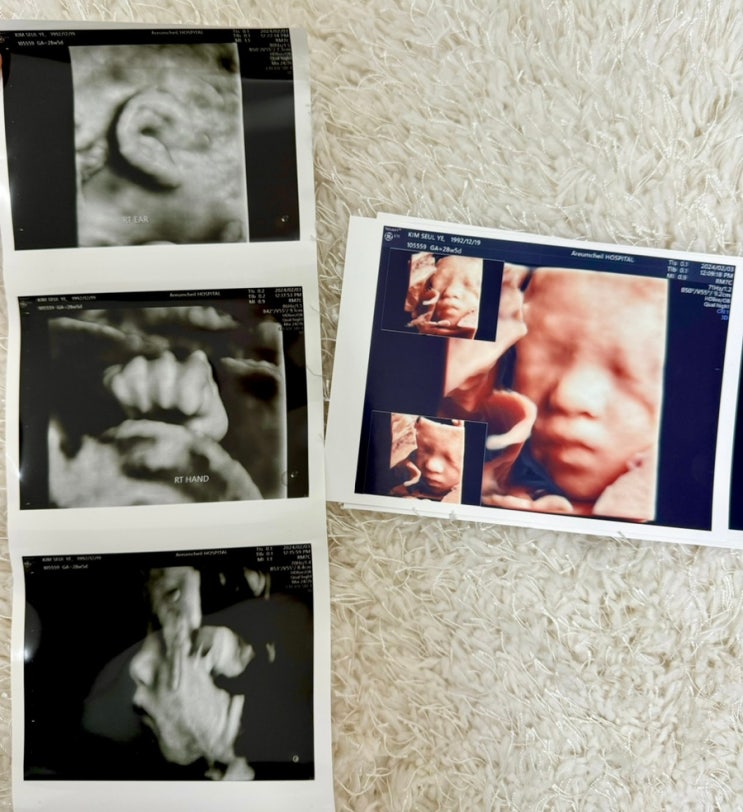

무사히 30주를 맞이하며

드디어 앞자리 3 진입 ~~~~! 11월 중순 그러니까 16주부터 경부길이가 짧다는 소견이 있었다 당시에는 3cm ...